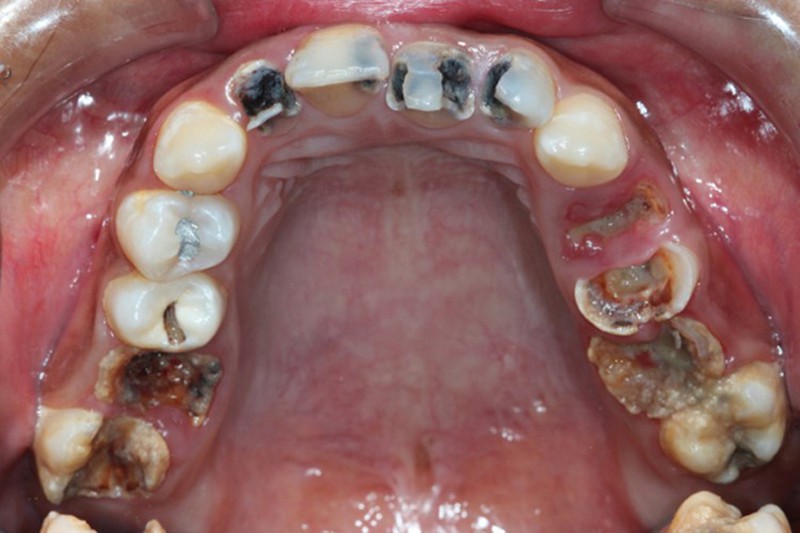

Căn bệnh khiến mỗi người Việt Nam mất hơn 6 chiếc răng

Theo kết quả điều tra răng miệng gần đây cho thấy, toàn quốc có trên 60% người bị sâu răng. Trung bình 18 tuổi đã có khoảng 2,84 người bị sâu răng; 45 tuổi đã sâu 8,93 răng. Đặc biệt tỷ lệ mất răng do sâu cũng đáng báo động.

Cụ thể 18 tuổi trung bình đã bị mất 1 cái răng, 45 tuổi đã mất 6,64 cái răng. Đặc biệt, có khoảng 85% trẻ em từ 6-8 tuổi bị sâu răng, mỗi trẻ trung bình có tới 6 răng sâu và phần lớn bệnh nhân mắc bệnh không được điều trị kịp thời. Nếu không được điều trị sẽ ảnh hưởng đến sức khỏe, thẩm mỹ.